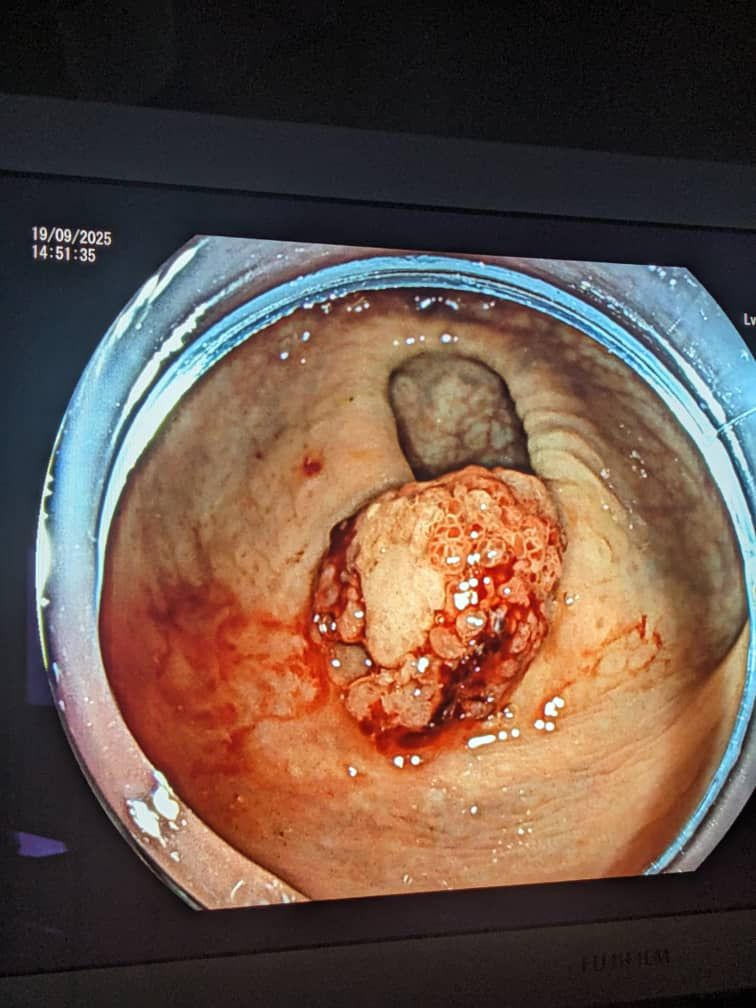

Mu Rwanda hakozwe bwa mbere ubuvuzi bwa kanseri ifata mu rura runini hatabayeho kubaga umurwayi, ibizwi nka Endoscopic Submucosal Dissection (ESD).

Mu butumwa ibitaro byitiriwe Umwami Faisal byasangije ku rubuga rwa X, bavuze ko ubu buvuzi bwakozwe kandi bukagenda neza.

Ubu buvuzi bufasha mu kuvura kanseri iri mu bice bigize urwungano ngogozi nko mu gifu, urura runini n’ibindi bice ariko hatabayeho kubaga ibyo bice ngo urwaye abe yanahindurirwa ahasohokera imyanda yo mu musarani.

Uburyo bikorwamo hifashishwa aga ‘tube’ kariho ibyuma byifashishwa mu buvuzi ndetse na camera, bikoherezwa mu mubiri binyujijwe mu gice cyo hasi ahanyura imyanda, izo camera ziba zihujwe na mudasobwa ku buryo zitanga amakuru.

Ibyuma by’ubuvuzi bifasha mu gukuramo ikibyimba cyose cya kanseri bitabangamiye ibindi ibice by’umubiri, iyo birangiye umurwayi akomeza gukurikiranwa kugirango hamenywe neza niba yarakize.